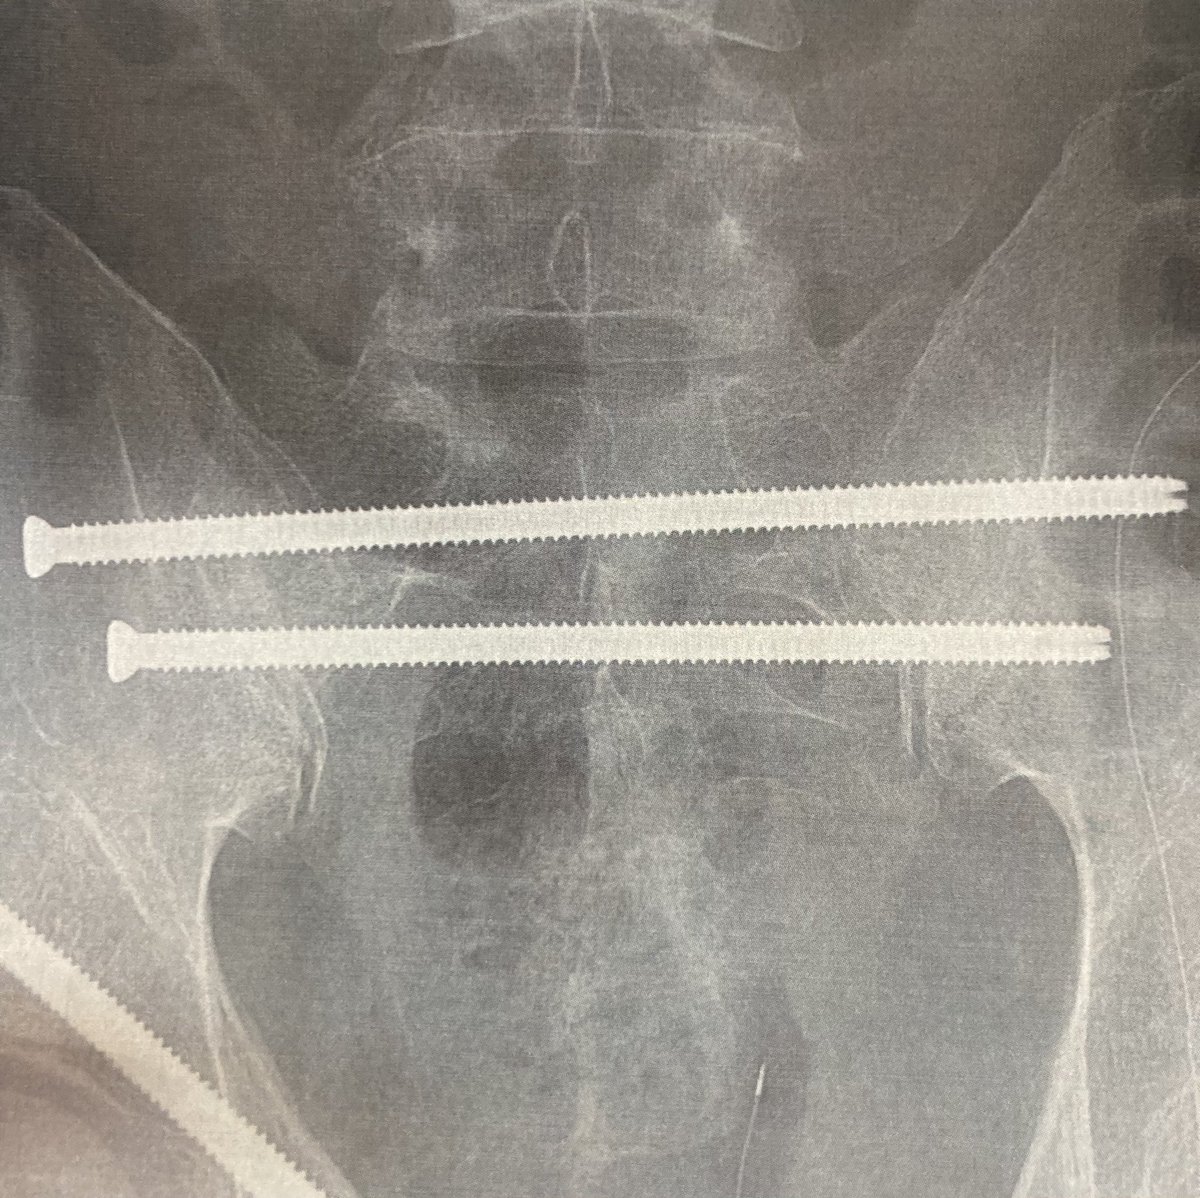

手術は無事に終わりました。 術後は麻酔から完全に覚めるまでに時間がかかり、泥のように眠り続けました。 意識が落ちたら呼吸が止まるのではと感じるほどの酔いに不安を覚えましたが、今朝はスッキリ目覚めています。 元気です。

明日は大事な一日になります。 転院搬送を経ての手術、 もう感謝の気持ちしかありません。 相変わらず人生のスパイスは激辛でした。でも死ぬ前にはきっと良い人生だったなと思えているはずだから。 祈るような気持ちで、手術に臨んできます。

2日間過ごしたICU(集中治療室)から一般病棟に移り、外の世界と連絡が取れるようになりました。 今回とてつもない誕生日プレゼントをもらいましたが、天を恨んでも仕方がない。先ずはありのままを受け入れること、許すことなのかな。 生きてます